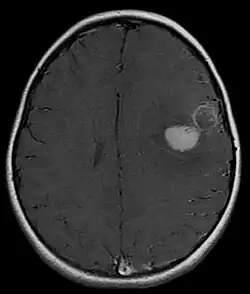

Primitive neuroectodermal tumor of the central nervous system in a 5-year-old

Magnetic resonance image of PNET

Most children that develop primitive neuroectodermal tumors are diagnosed early in life, usually at around 3–6.8 years of age.[2] Symptoms patients present at time of diagnosis include irritable mood, visual difficulties, lethargy, and ataxia.[2] The circumference of the patient's head might also become enlarged and they might be subject to seizures, especially if they have less than one year of life.[2]

Several analysis can be used to determine the presence of the disease. Physical examinations showing papilledema, visual field defects, cranial nerves palsy, dysphasia, and focal neurological deficits are evidences for possible tumor.[2] PNETs can also be spotted through computed tomography (CT) and magnetic resonance imaging (MRI).[2] In images produced by MRIs, an irregular augmentation among a solid mass will indicated the presence of tumor.[3] However, the results of MRIs are usually ambiguous in defining the presence for this specific tumor.[2] In CT scans, the presence of PNETs will be indicated by an elevated density and an increase in volume of the brain.[2] The CT scan can also show calcification,[3] which is present in 41-44% of PNET cases.[2] Since the tumor can be replicated in other parts of the nervous system through the cerebrospinal fluid (CSF), a CSF analysis can also be conducted.[2] A spinal MRI is a fourth type of analysis that is useful in investigating the level of tumor propagation to the spinal cord.[2]